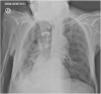

A follow-up Chest X-ray (48h hours later) revealed a significant improvement, with complete resolution of the left lung atelectasis (Fig. 2).